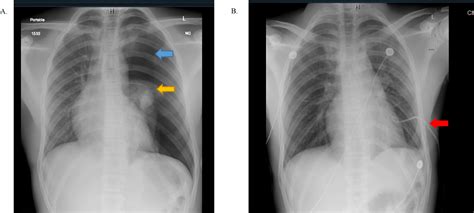

• Chest X-ray: This is often the first-line imaging study used to diagnose pneumothorax. It can detect the presence of air in the pleural space and assess the size of the pneumothorax.

Physical examination may reveal decreased breath sounds on the affected side, hyperresonance to percussion, and tracheal deviation in cases of tension pneumothorax.